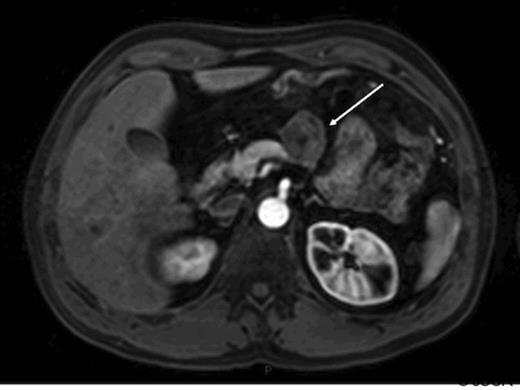

A 42 year old man presented with a history of flushing and sweats and was found on investigation to have a lesion associated with the body of his pancreas. His gut hormone profile was normal and urinary 5-hydroxy indole acetic acid levels were similarly within the normal range. He underwent biopsy of the lesion via endoscopic ultrasound which confirmed the presence of a neuroendocrine tumour of carcinoid subtype. He underwent a spleen preserving distal pancreatectomy for a carcinoid tumour situated in the midbody of the pancreas (fig1).

Arterial phase gadolinium enhanced MRI demonstrating primary tumour (arrow)